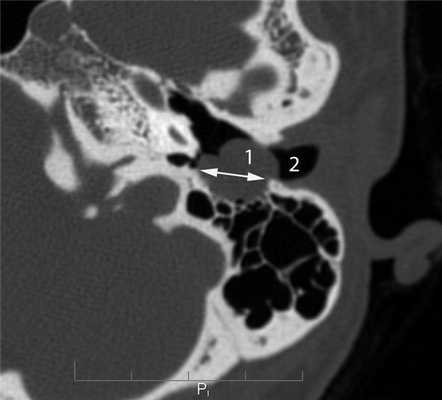

Невринома лицевого нерва в отличие от злокачественной опухоли характеризуется на КТ наличием в височной кости мягкотканного образования, имеющего достаточно ровные четкие контуры. Образование располагается по ходу одной из частей канала лицевого нерва и вызывает разрушение его костных стенок [5, 6, 9]. Невринома мастоидальной части лицевого нерва вследствие близкого расположения к наружному слуховому проходу часто распространяется в его просвет в виде округлого образования, вызывающего разрушение задней стенки (рис. 6). Рисунок 6. Невринома лицевого нерва. Аксиальная проекция левой височной кости. По ходу мастоидальной части канала лицевого нерва определяется объемное образование (1), распространяющееся в наружный слуховой проход (2). Стенки мастоидальной части канала лицевого нерва и задняя стенка наружного слухового прохода разрушены (стрелка). При клиническом осмотре в наружном слуховом проходе определяется образование плотноэластической консистенции на широком основании.